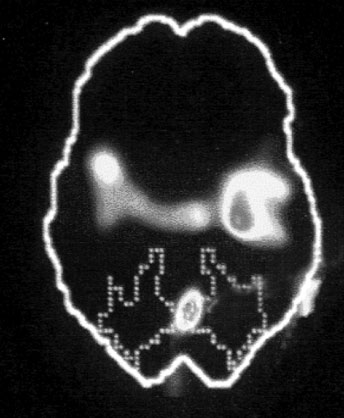

Больше всего из полученных нами результатов нас поразила белая точка в левой фронтальной доле коры, так называемой зоне Брока. В данном случае изменение цвета означает значительный спад активности в этой области мозга.

Зона Брока – это один из речевых центров мозга, который зачастую бывает затронут у людей, перенесших инсульт, когда этот участок оказывается отрезан от кровотока. Без нормально функционирующей зоны Брока человек неспособен выражать словами свои мысли и чувства. Наши снимки показали, что при активации болезненных воспоминаний зона Брока отключалась.

Когда слова подводят, центральное место в переживаниях занимают навязчивые образы, которые впоследствии преследуют нас в виде ночных кошмаров и болезненных живых воспоминаний. Если у наших участников отключалась зона Брока, то другой участок мозга под названием поле Бродмана 19[16] в этот момент активировался. Эта область зрительной коры регистрирует образы, когда они впервые попадают в мозг. Мы были удивлены увидеть активацию этой области спустя столь долгое время после изначально пережитой травмы. Обычно необработанные образы, зарегистрированные в поле 19, быстро распределяются по остальным участкам мозга, которые пытаются осмыслить увиденное. Опять-таки, мы стали свидетелями того, как участок мозга зажигается, словно человек переживает свою психологическую травму прямо сейчас.

Сдвиг в одну сторону мозга

Снимки также показали, что во время этих живых болезненных воспоминаний у наших подопытных активировалась лишь правая часть мозга. В настоящий момент имеется множество научной и популярной литературы на тему различий между правым и левым полушарием. В начале девяностых мне доводилось слышать, что кто-то начал делить мир на людей с развитым левым (преобладает рациональное мышление, логика) и правым (интуиция, творческие способности) полушариями, однако тогда я не придал этой идее особого значения. Тем не менее наши снимки явно демонстрировали, что образы о пережитой травме активируют правое полушарие мозга, отключая при этом левое.